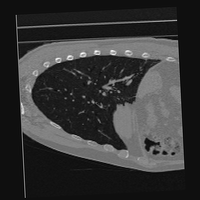

Exp. 3: Adult thorax data: To show the versatility of our approach we also apply it to adult thorax scans. For this experiment no organ specific training is performed but the whole volume is used. We evaluate reconstruction performance similar to Exp. 1 and prediction performance when is projected on an external plane, comparable to X-Ray examination using C-Arms. The latter provides insights about our method’s performance when applied to interventional settings in contrast to motion compensation problems. 60 healthy adult thorax scans were randomly selected, 51 scans used for and nine scans used for . Each scan is intensity normalised and resampled in a volume of with spacing . Using the Fibonacci sampling method, 25 sampling plane of size , evenly spaced between -50 and +50, were rotated over 500 normals. Training took approximately 20 hours for 60 epochs. Fig. 4c shows an example reconstruction result gaining 28dB PSNR with additional SVR. prediction takes approx. 20 ms/slice for this data.

0..5.3 Exp. 3:

We replicated the experiment on adult thorax data without specifically segmented organs. This approach was applied to CT acquisition, shown in Fig 13 and 14, as well as Digitally Reconstructed Radiographs generated using Siddon-Jacobs Ray Tracing shown in Fig. 16.